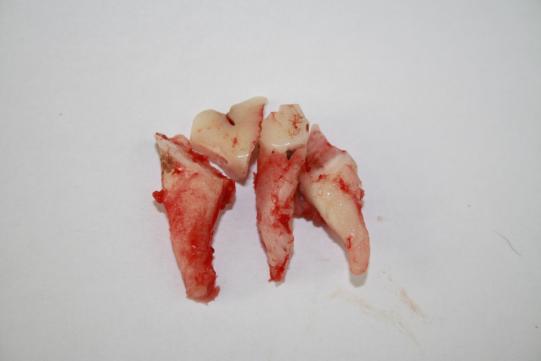

Mittels sogenannter Separierung und Aufklappung wird der Zahn entfernt: Als erstes wird ein Schleimhautlappen vorsichtig vom z.T. schon fehlenden Kieferknochen gelöst. Noch vorhandener Knochen wird mit einem Bohrer weggefräst, so dass die drei Wurzeln des Zahnes freigelegt werden. Nach Zersägen des Zahnes in 4 Teile (3 Wurzelteile sowie ein Kronenteil, welches zur besseren Übersicht entfernt wird) werden die angegriffenen Wurzeln sorgfältig aus den Wurzelhöhlen gehoben. Nun wird mittels scharfem Löffel und Bohrer sämtliches Entzündungs- und Granulationsgewebe aus der Region entfernt und die Knochenwunde mit einem Desinfektionsmittel gespült. Anschliessend wird der grosse Schleimhaut- und Knochendefekt mit dem zuvor gelösten Schleimhautlappen geschlossen; die hierzu verwendeten feinen Fäden lösen sich mit der Zeit von selbst auf. Jessy erhält Schmerzmittel und ein Antibiotikum; in aller Regel heilt der Abszess so in der Folge problemlos ab.